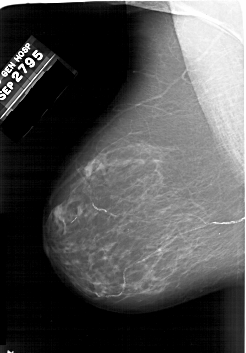

A_1895_1.RIGHT_MLO

RIGHT_MLO LINES 6016 PIXELS_PER_LINE 4276 BITS_PER_PIXEL 12 RESOLUTION 43.5 OVERLAY